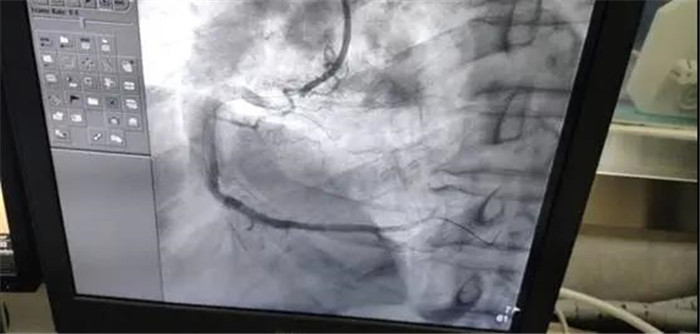

10月25日,庐江县中医院心血管内科团队成功开展首例急性心肌梗死急诊冠脉造影+冠状动脉支架植入术。患者为老年男性,因反复心慌胸闷2月,加重7小时入住我院心血管科。心电图示:下壁心肌梗死,肌钙蛋白阳性,心肌标志物升高,心室率80次/分;结合病史考虑冠心病,急性心肌梗死。

心血管内科团队仔细分析患者病情,严格评估,精心制定了合理的治疗方案。10月25日,在DSA下,行急性心肌梗死介入手术,术中抽出了血栓,打通了血管,手术时间50分。手术非常成功,术后患者恢复良好。